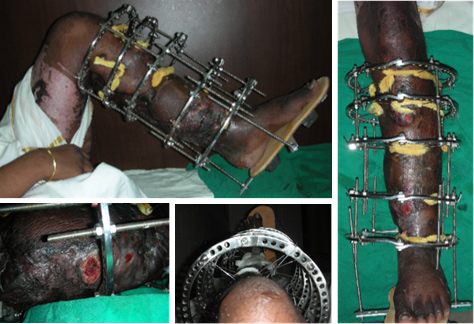

| Ulnar plate removed and fixator applied |

| Pinsites get worse, Radius sequestrating |

| Clinical Appearance and pinsites at presentation |